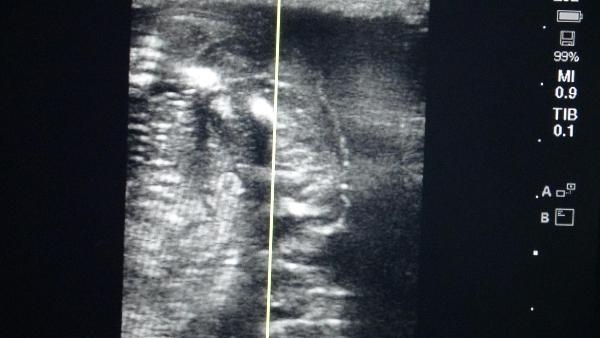

"Embriyo transfer kateteri yardımıyla alıcı kısraklara embriyolar transfer edildi. Transfer sonrasındaki 4'üncü günde ilk gebelik kontrolleri ultrasonografi yardımıyla yapıldı. Yapılan çalışmada bir adet donör ve 7 adet alıcı kısrak kullanıldı. Toplamda 6 adet yıkama gerçekleştirildi ve bunlardan 3'ünde embriyo elde edilerek alıcılara transferi gerçekleştirildi. Bu 3 kısraktan bir tanesinde 'embryonic rezorpsiyon' gerçekleşti, yani transfere rağmen gebelik devam etmedi. Diğer 2 kısrağın gebeliği ise sağlıklı bir şekilde devam ediyor. Elde edilen gebelikler Türkiye'de atlarda embriyo transferi yoluyla üretilen ilk gebeliklerdir. 8 ay sonrasında doğacak taylar ise Türkiye'nin ilk tüp tayları olarak kayda geçecek."